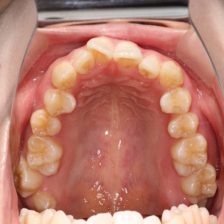

治療の前にはマイクロスコープや一眼レフカメラでお口の中を撮影して、現状をご確認いただきます。さらに患者さまのお悩みやご希望をしっかりうかがい、的確な治療法をご提案いたします。

予防歯科

矯正歯科

症例集